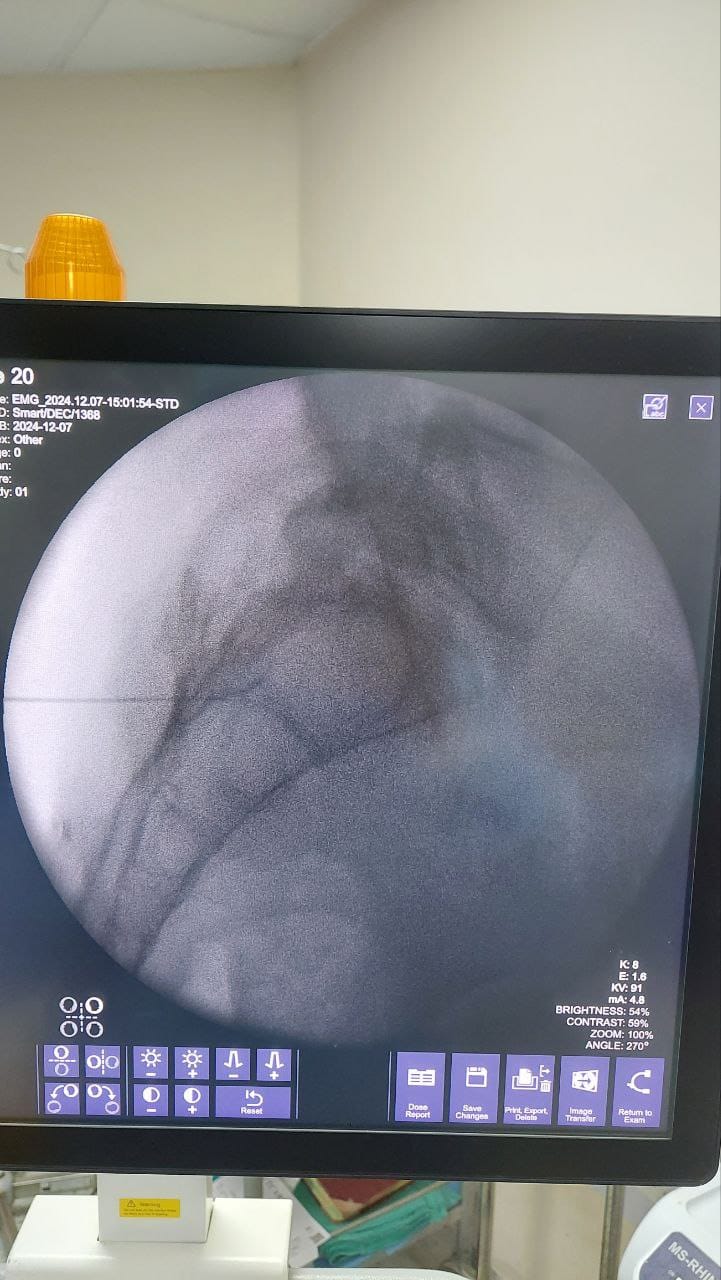

Struggling with chronic pain? Get advanced, personalised pain management from Dr. Manish De, one of Kolkata’s leading pain specialists. From knee pain, heel pain, low back pain, frozen shoulder, migraines, cancer pain to post-TKR persistent pain—Dr. De offers safe, evidence-based treatments across multiple locations: